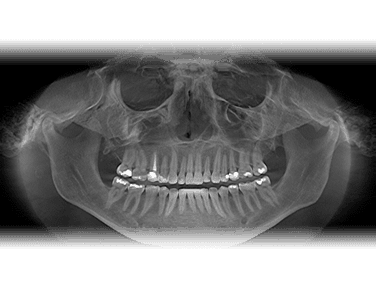

For the first time in the 100-year history of dental X-rays (radiography), an extraordinary new technology surpasses the diagnostic abilities of traditional film. It does so with substantially less radiation exposure to you.. and us. This system has truly amazing diagnostic tools, making the image quality simply unmatched.

Lockheed Martin, the aerospace manufacturer of the Magellan Venus Spacecraft and the Hubble Telescope designed the digital X-ray sensor that is the heart of this technology. The sensor is very special as it has a uniquely shaped design for your optimum comfort. No more sharp edges like the old film had. This allows for increased positioning accuracy.

This system allows for the ability to instantly produce the very best possible diagnosis and produces up to 90% less radiation.